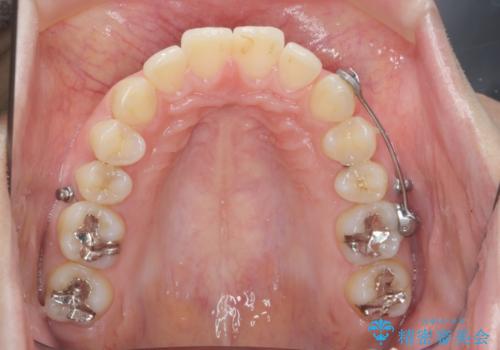

カリエール・マイクロインプラントを併用した歯の突出を改善する大きな遠心移動

- 口が閉じづらく、突出し歯が出っ歯に見えてしまうことの改善を求めて来院されました。

通常このような場合、抜歯してのワイヤー矯正治療も選択肢に入りますが、患者様の強い希望により抜歯を行わずマウスピースによる治療を選択しました。

カリエール・マイクロインプラントを用い、時間はかかりましたが大きく歯の後方移動が達成され、前歯の見た目が大きく改善されました。

大きな後方移動を達成するにはマイクロインプラントと日常的なゴムかけが大切です。